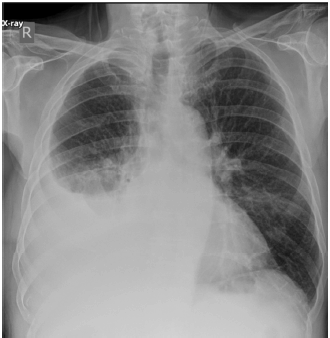

O paciente traz a seguinte radiografia de tórax:

Internet: < https://radiopaedia.org/cases/151132/studies/125463?lang=us >.